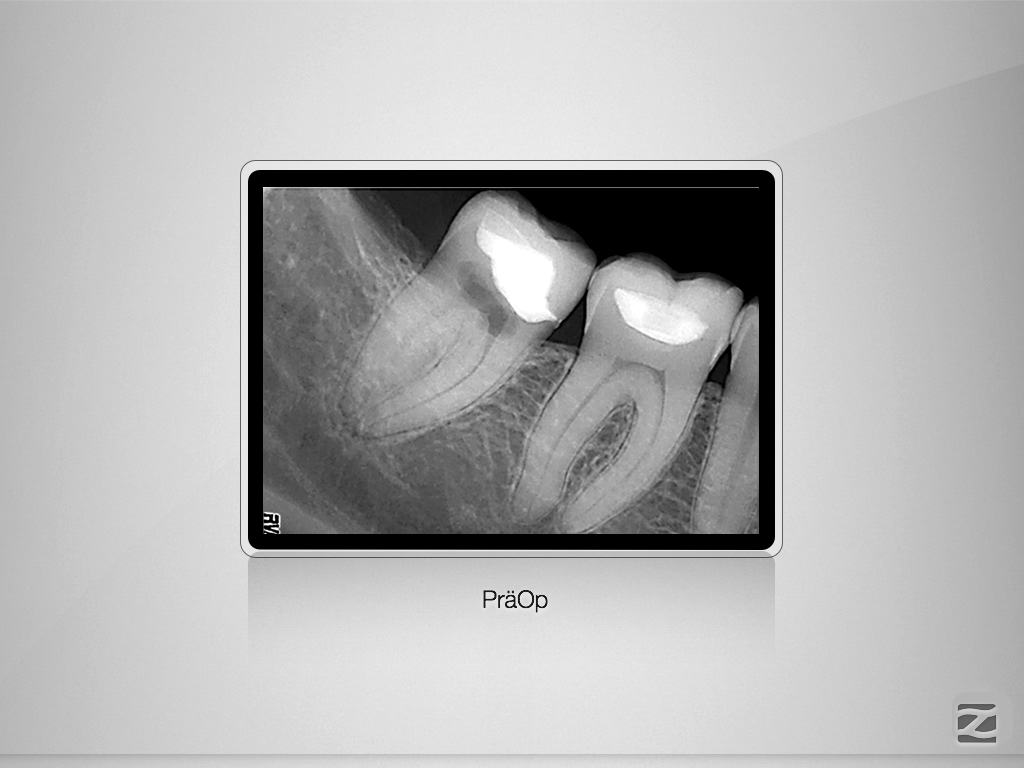

Interne Resorption 10-Jahres-Recall